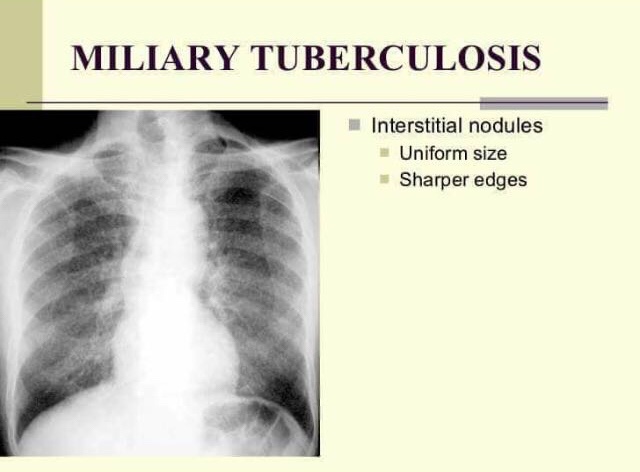

- Miliary Tuberculosis –

• uniform size and distribution throughout both lungs